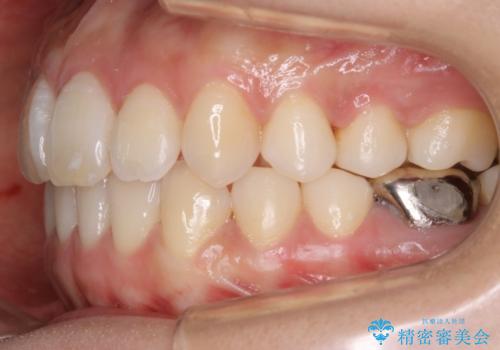

遠心移動

非抜歯で矯正を行う場合にガタつきの改善に必要なスペースを作るために歯の遠心移動を行います。

最初の位置から奥に歯を移動させていくことで前歯のガタつきを改善したり、前歯の位置を後方に移動させることが可能となります。

その反面、歯の移動距離が大きくなるので治療期間が長くなる傾向があり、その分コントロールの難しさが上がることが予想されます。